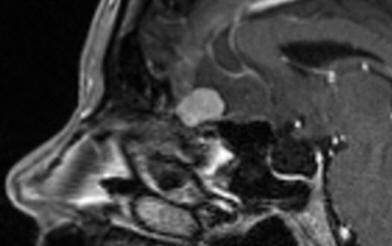

09-SEPTEMBER-2019  ZAINAB ABDALLA WADI  51 YEARS  PROGRESSING OLFACTORY GROOVE MENINGIOMA.

The patient came to the clinic 15-Sptember-2018 complaining of absence attacks for 2 years  every week with tonic-clonic generalization happening the last month. MRI of the brain bad quality performed 04-April-2018 was not informative and EEG 20-September-2016 confirming right temporal lobe sharp activity. On examination at that time, she had bilateral anosmia with tinnitus left ear. The patient is a known diabetic for 2 years and hypertensive for 3 years and cath done 6 months ago and coagulation for arrhythmia performed. The patient using trileptal 300 twice daily. The patient was sent for investigations and MRI of the brain performed 15-September -2018 showing sinusitis with partial empty sella and olfactory groove meningioma 13.4 mmx11.3 mm. Cardiac evaluation was uneventful except for prescribing blopress plus 16/12.5 once daily. The trileptal was prescribed three times a day. It was decided to put the patient under observation to see the progression of the tumor.

The patient was sent for MRI evaluation , which was performed the same day showing enlargement of the tumor 15.4mm x 17.1mm. The tumor enlargement was 1.78 for what it was decided to perform surgery. Tegretol level was 0.22 for what it was advised to increase the trileptal to 1+1+2.

The olfactory groove meningioma in frontal and Saggital projections with contrast.